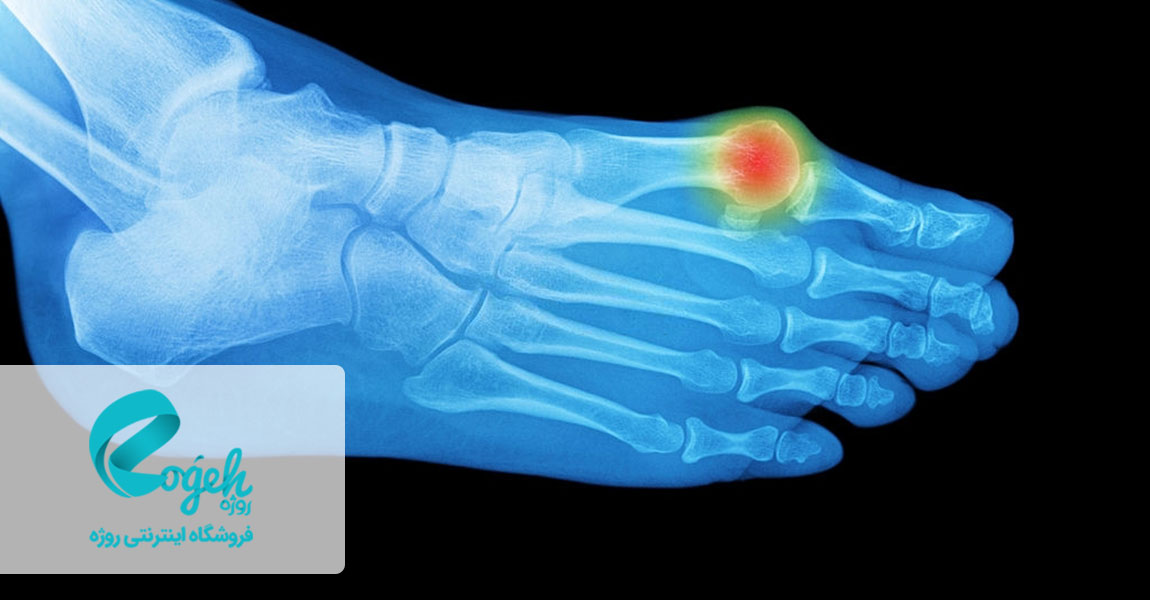

درمان انحراف شست پا معضل بسیاری از مردم است. چرا که بیرون زدگی استخوان انگشت، علاوه بر ظاهر ناخوشایندی که دارد، وقتی که کفش میپوشید خیلی آزاردهنده است. بونیون (bunion) تودهای استخوانی است که در مفصل واقع در قاعدهی شست پا ایجاد میشود. این توده زمانی به وجود میآید که شست پا به سمت انگشت مجاورش فشار دادهشود و مفصل شست برجسته و بزرگ شود. این عارضه، گاهی با علائمی همراه است. گاهاً هم بدون علائم خواهد بود.

انحراف شست پا یک برآمدگی استخوانی در مفصل پایهی انگشت بزرگ است. انحراف شست پا زمانی ایجاد میشود که انگشت بزرگ پا به انگشت کناری فشار وارد کرده و باعث بزرگ شدگی و بیرون زدگی مفصل شست پا شود. در این حالت پوست انگشت دارای انحراف، قرمزی و تورم خواهد شد. پوشیدن کفشهای تنگ و باریک باعث ایجاد انحراف و یا تشدید انحراف موجود در شست پا میشود. همچنین انحراف شست پا در نتیجهی وجود یک مشکل ساختاری ژنتیکی، فشار به پا یا مشکلاتی همچون آرتریت ایجاد میشود. درمان انحراف شست پا بسیار ضروری است چرا که این بیماری رفته رفته شدیدتر میشود.

عدم توجه به درمان انحراف انگشت شست پا میتواند موجب ناراحتی در بورس (کیسهی پر از مایع دربرگیرندهی مفصل) شود. بدین ترتیب بورس دچار التهاب و ورم شده و باعث ایجاد درد و حساسیت نسبت به لمس در ناحیهی مفصل میشود. همچنین ممکن است مفاصل دیگر انگشتان پا به محدودیتهای حرکتی دچار شوند. به این عارضه بورسیت گفته میشود.